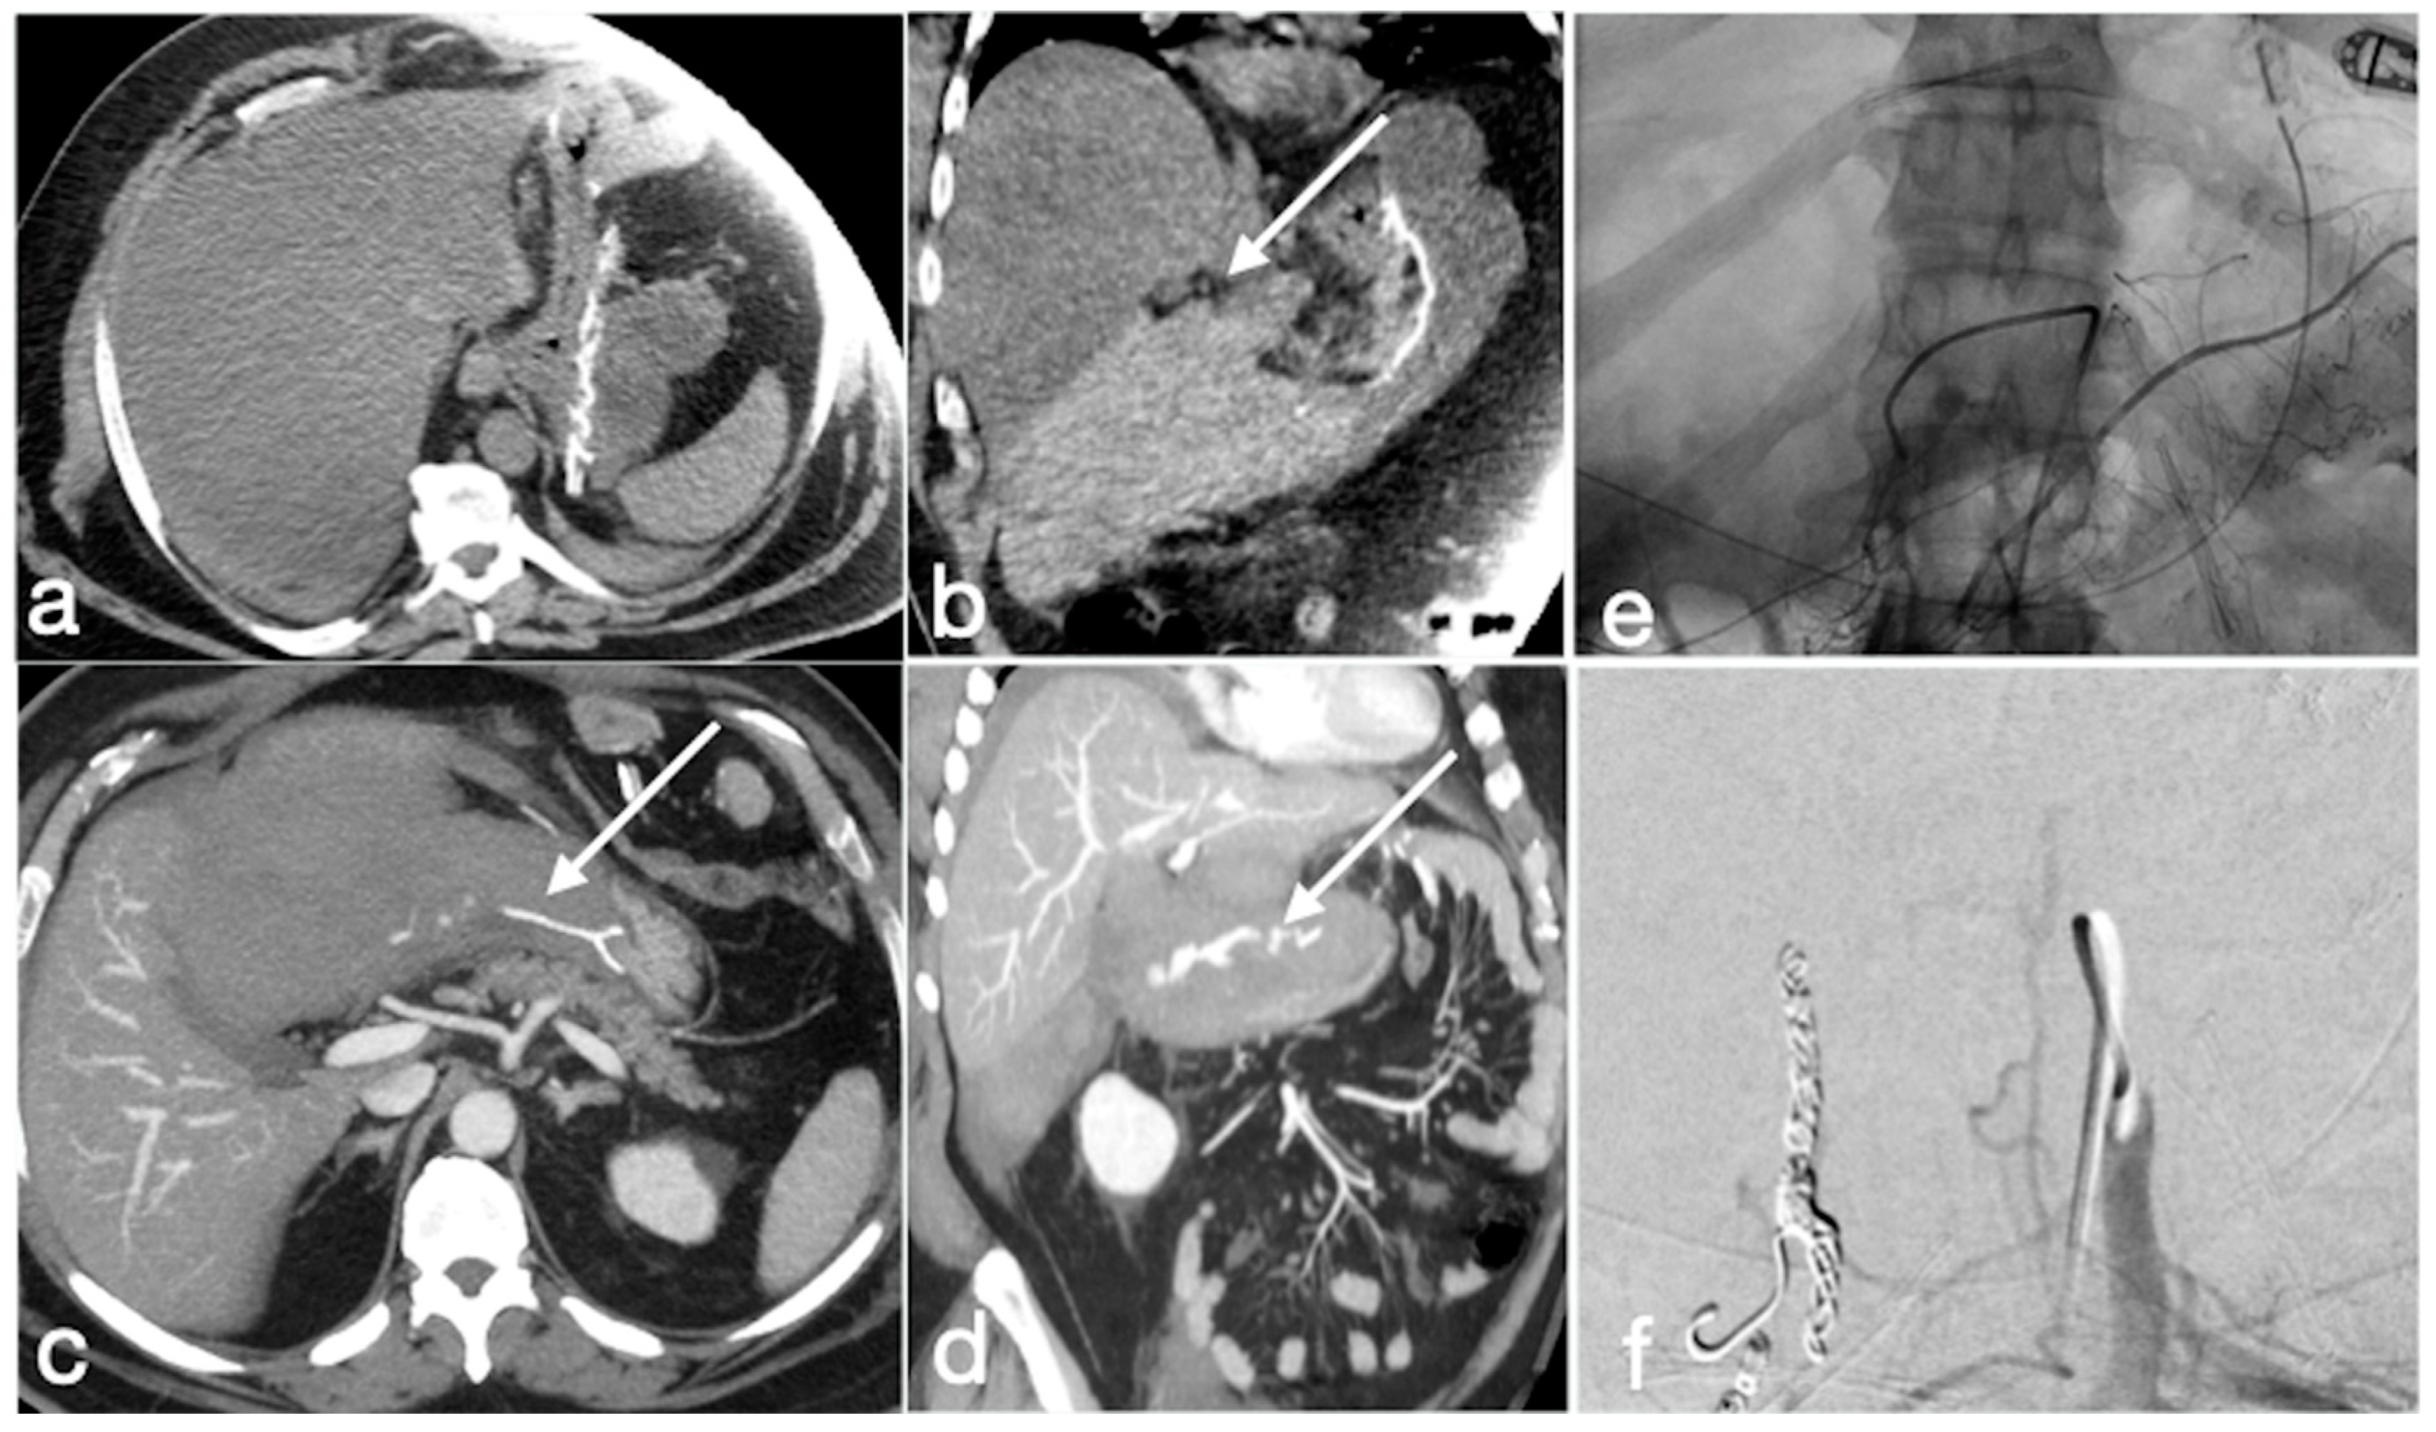

3.4. Unexpected Complication